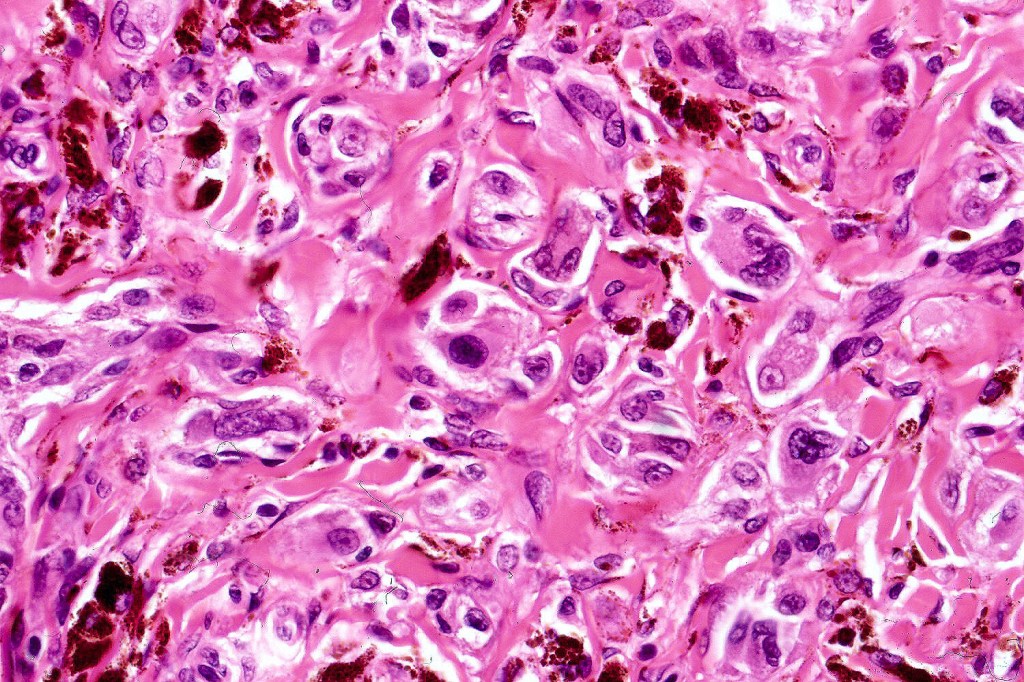

•Admixture of spindle cells, pigmented bipolar or dendritic cells & melanophages

•Cytoplasm is pale and nuclei are small with inconspicuous nucleoli

•An alveolar pattern is characteristic particularly with clear cell nodules

•Multinucleate giant cells sometimes present

•Stromal fibrosis, myxoid change, vascular hyalinization with cyst formation are often seen